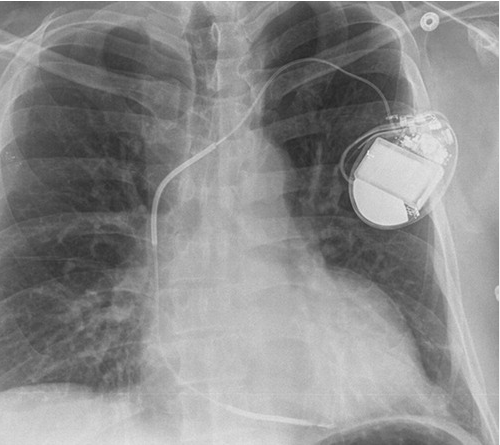

PTCA is sort of repair work done over the blocked area that restores the traffic(blood) flow. while CABG, diverts flow from the congestion or road closure, along a by- pass road, which rejoin the main road later. These are called re-vascularisation procedures. Please note, both of them, never bother to find the status of micro-vascular integrity which form 95% of net coronary vascular surface area.